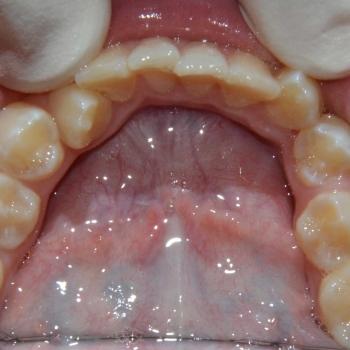

Kíra és édesanyja egy kollegám javaslatára kerestek fel a rögzített fogszabályzó számára legoptimálisabb időszakban, a tejfogak leváltása után, de még a 7-es fog előtörése előtt. Az első konzultáció alkalmával fény derült az alsó és felső fogív nagymértékű torlódására, a jobb felső szemfog kiszorult helyzetére és következményes felső középvonal eltolódására, illetve az enyhe mélyharapásra. A röntgenek kiértékelése után ez a kórkép kiegészült az alsó és felső metszőfogak hátradőlt pozíciójával, ami a kezelést nagyban megkönnyítette, mert lehetőséget adott mindkét fogív meghosszabbítására, így helynyerésre a torlódott fogazat számára.

Ennek megfelelően a kezelés kizárólag alsó és felső hagyományos fém fogszabályozót tartalmazott bite turbo harapásemeléssel kiegészítve, illetve a harapás finombeállításához különböző intermaxilláris gumihúzásokkal.

A kezelés megoldotta az összes fogszabályozással kapcsolatos problémát, így egy funkcionálisan és esztétikailag is megfelelő harapást kaptunk.

A kezelés teljes időtartama: 2 év